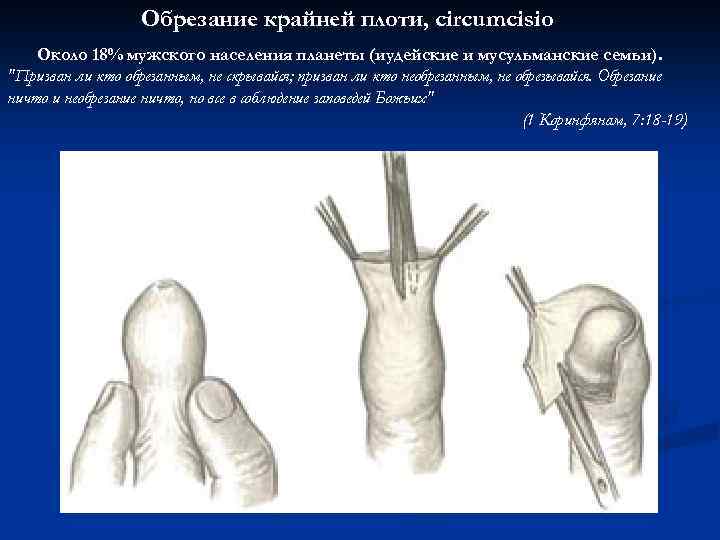

Обрезание крайней плоти, circumcisio Около 18% мужского населения планеты (иудейские и мусульманские семьи). "Призван ли кто обрезанным, не скрывайся; призван ли кто необрезанным, не обрезывайся. Обрезание ничто и необрезание ничто, но все в соблюдение заповедей Божьих" (1 Коринфянам, 7: 18 -19)

Обрезание крайней плоти, circumcisio Около 18% мужского населения планеты (иудейские и мусульманские семьи). "Призван ли кто обрезанным, не скрывайся; призван ли кто необрезанным, не обрезывайся. Обрезание ничто и необрезание ничто, но все в соблюдение заповедей Божьих" (1 Коринфянам, 7: 18 -19)